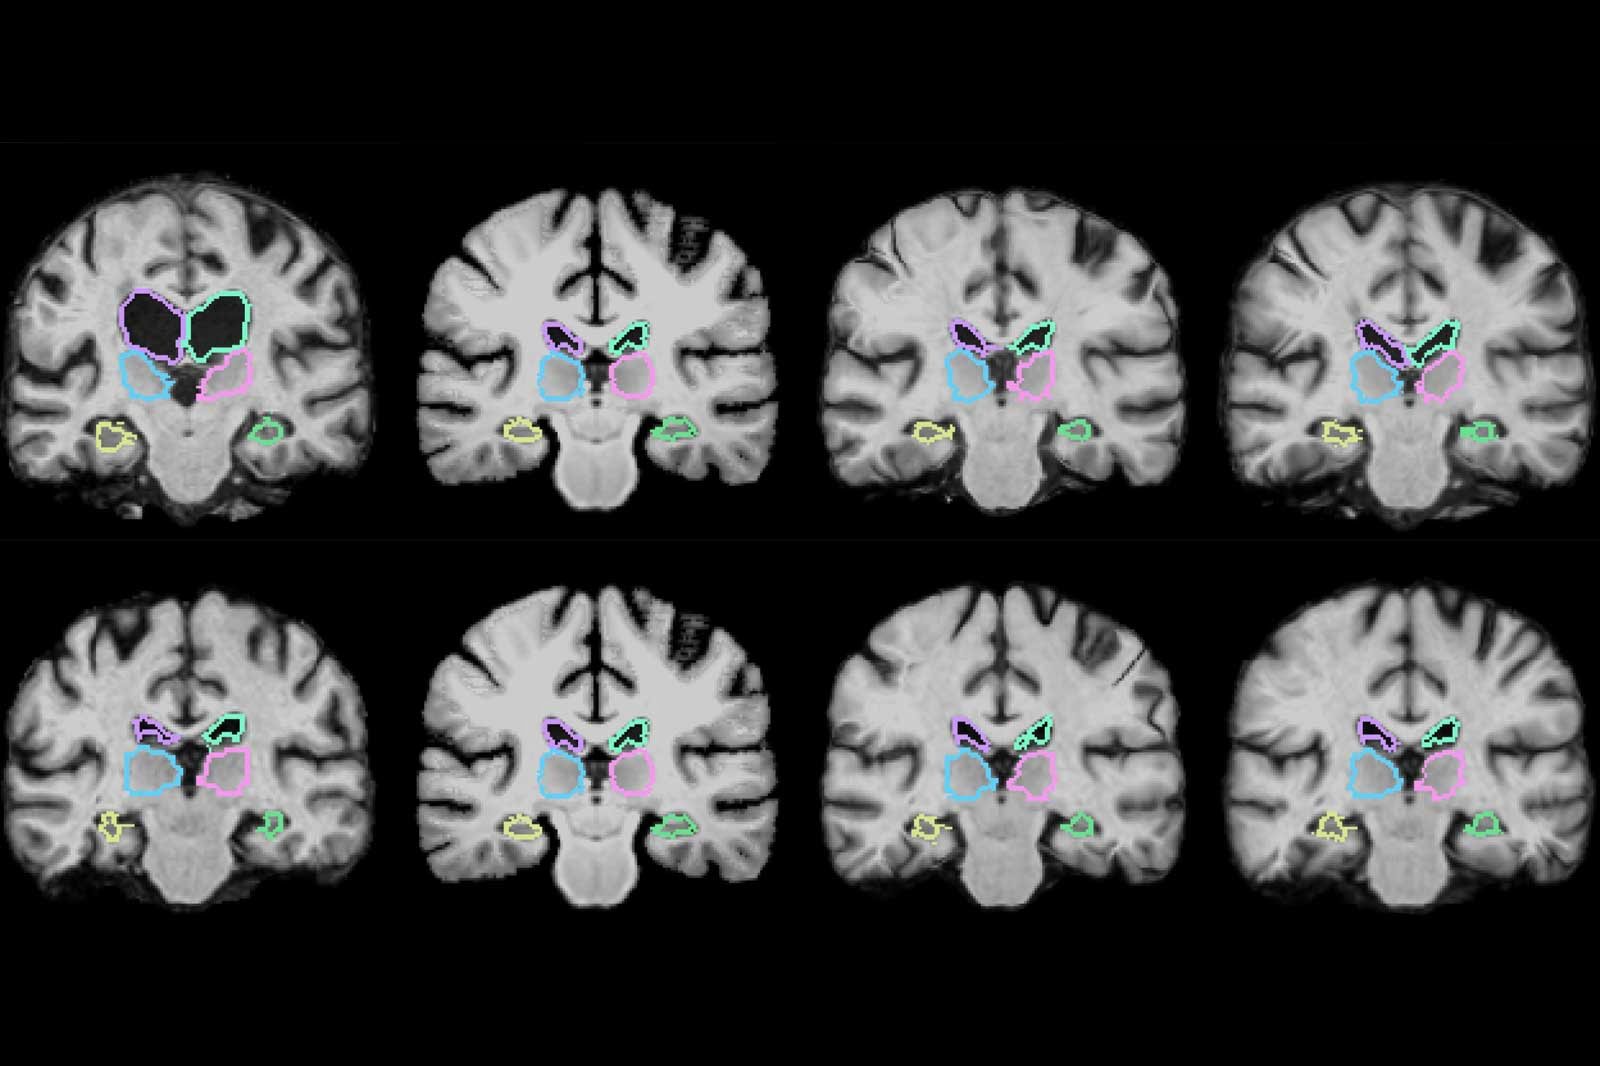

تیم تحقیقاتی MIT یک الگوریتم یادگیری ماشین را طراحی کرده است و این الگوریتم قادر است تا به عکس برداری و اسکن های سه بعدی با سرعت 1000 برابر بپردازد. همچنین این الگوریتم علاوه بر اسکن، به تجزیه و تحلیل نیز خواهد پرداخت. این تکنولوژی از طریق بررسی هزاران تصویر پزشکی آغاز شد و این الگوریتم چگونگی بررسی و تحلیل عکس ها را یاد گرفت. اکنون در این تکنولوژی قابلیت مقایسه دو اسکن سه بعدی به طور همزمان نیز ارائه شده است.

در حال حاضر تیم تحقیقاتی MIT بر روی اسکن مغز متمرکز شده اند اما این تکنولوژی برای اسکن ریه و بخش های دیگر بدن نیز کاربردی خواهد بود. به طور کلی این تکنولوژی در روند عمل های جراحی تاثیر بسزایی خواهد داشت و تحلیل و بررسی اسکن ها را برای پزشکان ساده تر خواهد کرد.